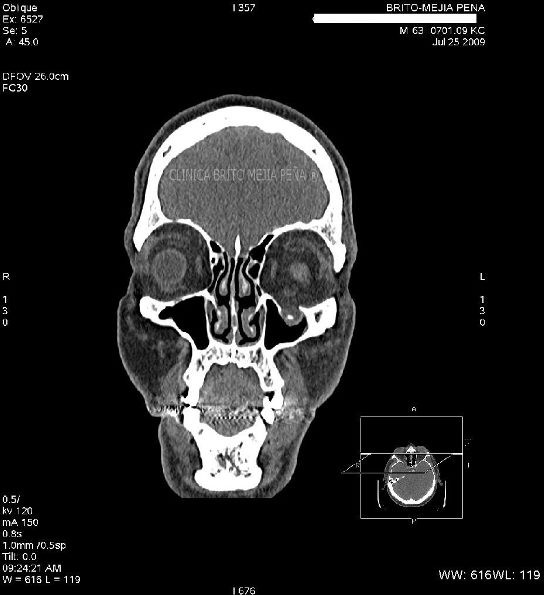

Fx piso órbita y hernia musculo

Fx piso órbita y hernia músculo sagital